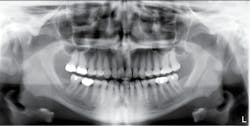

Radiographs—The teeth exhibit pulpal-root canal obliteration (see Figures 4, 5). The roots of the teeth are narrow and appear to be funnel-shaped. The crowns are large and there is constriction at the cervical neck of the tooth.